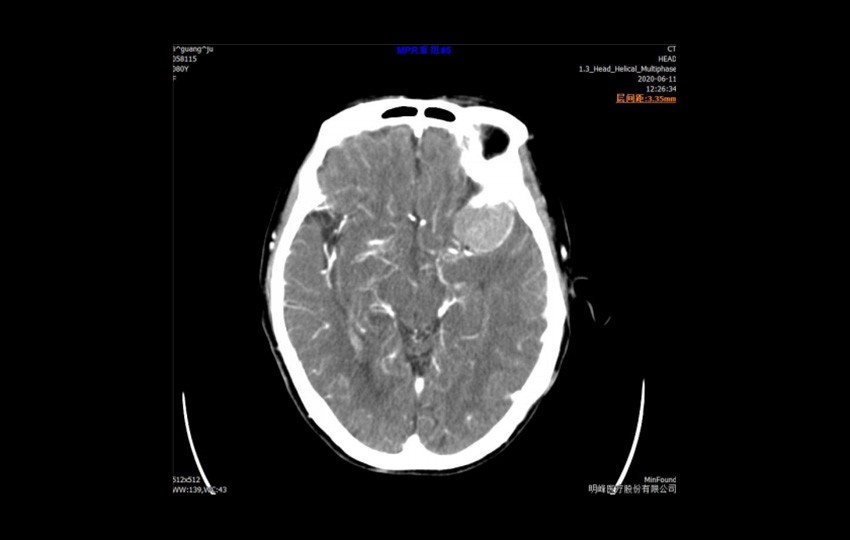

Caso 1-1<br>Meningioma

Caso 1-1

Meningioma